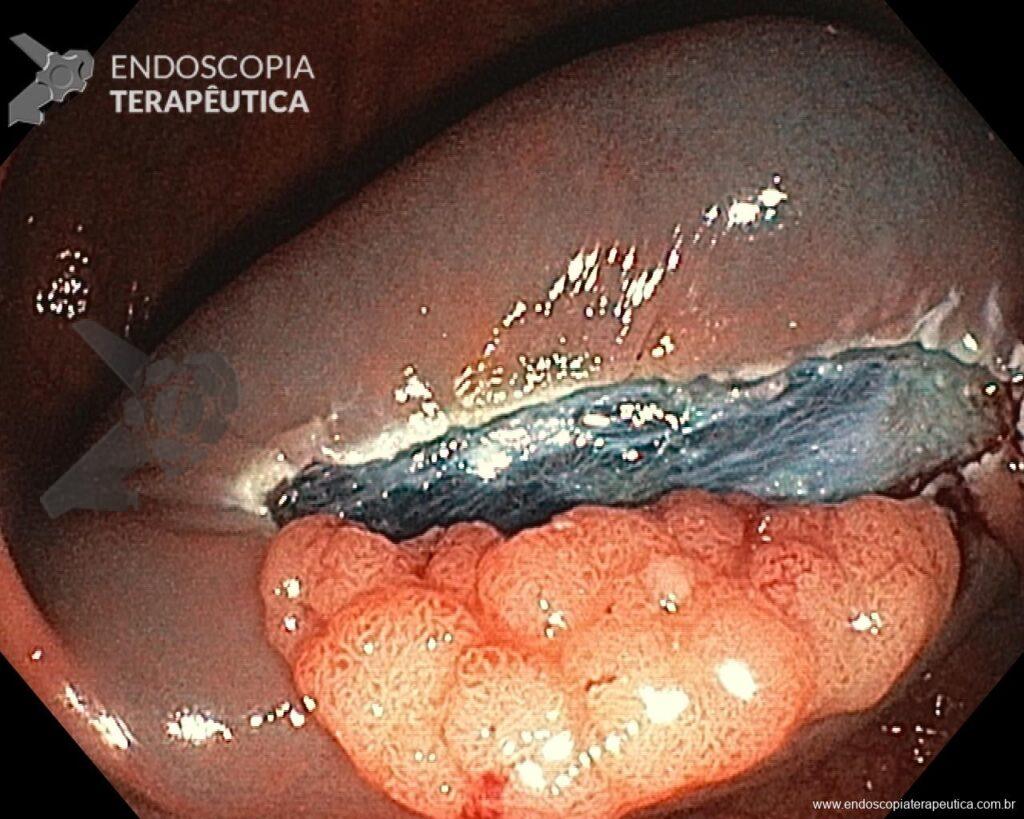

3. Elegir bien la asa.

Dependiendo de la morfología o tamaño del pólipo, seleccionar el asa más adecuada puede hacer la diferencia en el éxito del procedimiento y, por lo tanto, en los resultados. Asas rígidas pequeñas (10–20 mm) o grandes (25–33 mm) que poseen hilo trenzado deben ser preferidas para EPMR y EMR en bloque, respectivamente. Por otro lado, asas monofilamentarias pueden ser la mejor opción para capturar lesiones que poseen dificultad en elevar, como recurrencia tras EMR o situaciones que ya hubo intento de resección previa. Use el aparato como una extensión de su mano, colocándolo paralelo a la pared. Adapte el corte al plano de la lesión, fragmento por fragmento. Cuanto más ángulo cree entre el asa y la pared, mayor la probabilidad de involucrar la muscular propia. Cierre bien el asa para mantener la lesión en su lugar antes de resecarla. Esté consciente de la posibilidad de fibrosis submucosa resultante de la recolección de biopsias anteriores, intentos de resección previa y LST-NG, pues en estas situaciones la aprehensión del asa puede ser difícil, eventualmente necesitando de técnicas alternativas para la remoción de la lesión

Una vez elegida la técnica de EPMR, tenga en mente que el objetivo debe ser la remoción completa de la lesión con la mayor seguridad posible. Para eso, la estrategia correcta es fundamental: no haga la burbuja submucosa toda de una vez, en vez de eso, haga inyecciones sucesivas seguidas del corte, preferentemente en el sentido proximal-distal; siempre que disponible, dé preferencia a soluciones viscosas, que garanticen una mayor patencia de la burbuja; utilice un asa más pequeña (10-15 mm) para sujetar la ampolla formulada; además de facilitar la operación, reduce el riesgo de perforación al intentar sujetar toda la lesión inadvertidamente.